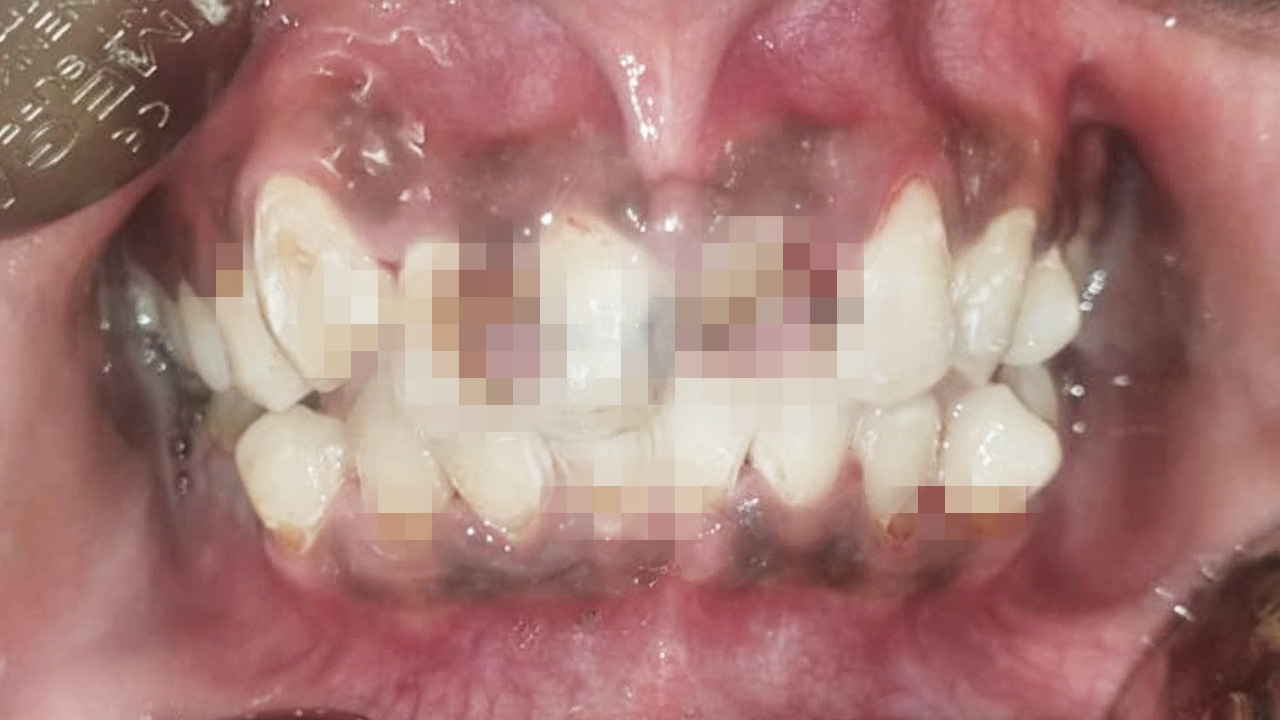

หมอโพสต์อุทาหรณ์โทษของการ "จัดฟันแฟชั่น" สภาพพังพินาศ ทำความสะอาดไม่ถูกวิธี ลวดดึงฟันผิดรูป ผุทะลุโพรงประสาทฟัน

เฟซบุ๊ก Pornputthi Puttaravuttiporn ซึ่งเป็นของคุณหมอโรงพยาบาลบุรีรัมย์ ได้เผยภาพอุทาหรณ์จากการจัดฟันแฟชั่น โดยระบุว่า เจอเคสจัดฟันแฟชั่น เป็นเคสที่คนไข้ไม่สามารถทำความสะอาดได้เลย ไม่ต้องพูดถึงฟันที่ออกมาเรียงตรงหน้ากระดานตามลวดตรงๆ ที่เค้าใส่เข้าไป

ความรู้สึกในฐานะหมอจัดฟันคนนึง เหล็กจัดฟันประโยชน์ก็มีมากมาย แต่โทษก็มหันต์เหมือนกันถ้าเอาไปใช้ในทางที่ผิด และก็ไม่ใส่ใจดูแลทำความสะอาด อยากให้ทุกคนที่เห็นโพสต์นี้ ได้ตระหนักถึงโทษของการจัดฟันแฟชั่น

สำหรับการรักษาคือ ถอดเครื่องมือจัดฟัน ขูดหินน้ำลาย และสอนคนไข้ทำความสะอาดช่องปาก และนัดกลับมาดูวันรุ่งขึ้น พบว่าคนไข้สามารถทำความสะอาดช่องปากได้ดีขึ้นมาก และมีฟันผุทะลุโพรงประสาทฟัน 2 ซี่

คนไข้ปฏิเสธการรักษารากฟัน จึงวางแผนถอนฟันทั้ง 2 ซี่ และคนไข้รายนี้ยังมีนัดทำฟันอย่างต่อเนื่อง ทั้งต้องอุดฟัน ใส่ฟันปลอม อย่างไรก็ตามโทษของการจัดฟันแฟชั่นนั้นมีหลายอย่าง ดังนี้